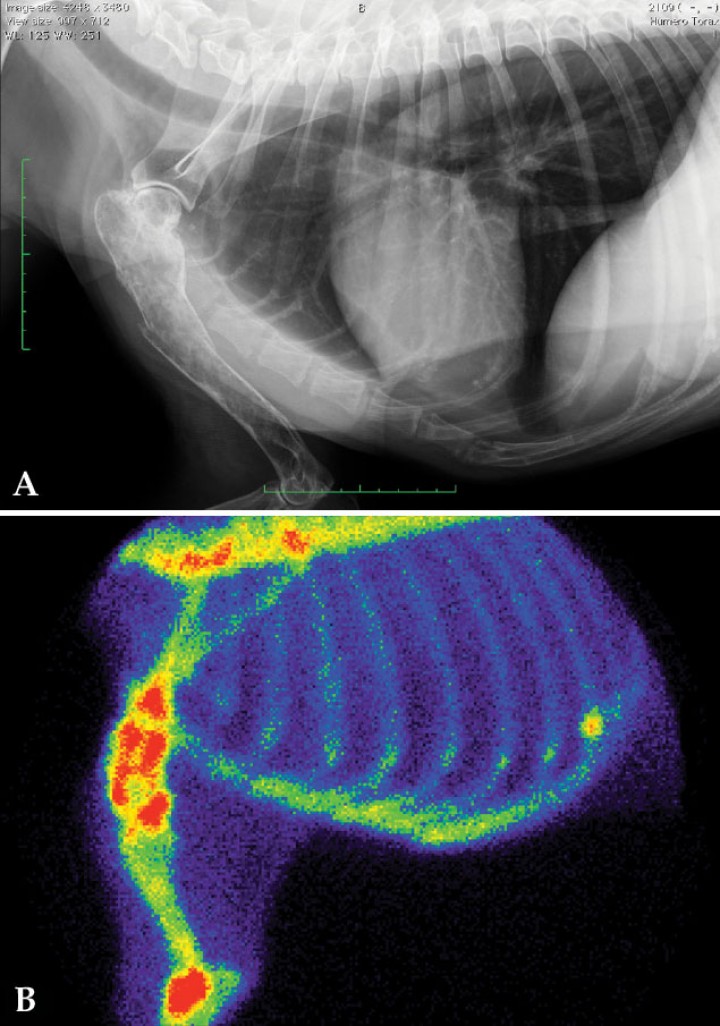

Posteriormente, se procesan las imágenes para obtener una imagen sumatoria de las adquisiciones dinámicas entre el minuto 1 y 3 post inyección (Fig. 9). Con ella, se calculan los valores de TFG tanto global como individual de cada riñón.[ Xifra MP, Serrano SI, Salgüero R, Broome MR. Valoración de la tasa de filtración glomerular (TFG) individual mediante gammagrafía renal; a propósito de un caso clínico. Clinfelivet; Revista clínica de medicina felina. 2019; 2: 13-17. , Gates GF. Glomerular filtration rate: estimation from fractional renal accumulation of 99mTc-DTPA (stannous). Am J Roent. 1982; 138:565-570. [PubMed] , Krawiec DR, Bardertscher RR, Twardock AR, Rubin SI, Gelberg HB. Evaluation of 99mTc-diethylenetriaminepentaacetic acid nuclear imaging for quantitative determination of glomerular filtration rate of dogs. Am J Vet Res. 1986; 47:2175-2179. [PubMed] , Uribe D, Krawiec DR, Twardock AR, Gelberg HB. Quantitative renal scintigraphic determination of the glomerular filtration rate in cats with normal and abnormal kidney function, using 99mTc-diethylenetriaminepentaacetic acid. Am J Vet Res 1992; 53(7):1101-7. [PubMed] ]

<p>Imagen sumatoria de la gammagrafía renal dinámica en una perra con valores de creatinina normal. Aumento de la actividad del flujo sanguíneo en el tórax por la disminución en el aclaramiento renal, con muy baja captación del radiofármaco por el riñón izquierdo. Tasas de filtración glomerular disminuidas: TFG global de 0,57 ml/min/kg (N: >3 ml/min/kg); TFG del riñón derecho de 0,50 ml/min/kg; TFG del riñón izquierdo de 0,07 ml/min/kg. El estudio es compatible con enfermedad renal subclínica, en la que el riñón izquierdo prácticamente no contribuye a la funcionalidad renal.</p>

Imagen sumatoria de la gammagrafía renal dinámica en una perra con valores de creatinina normal. Aumento de la actividad del flujo sanguíneo en el tórax por la disminución en el aclaramiento renal, con muy baja captación del radiofármaco por el riñón izquierdo. Tasas de filtración glomerular disminuidas: TFG global de 0,57 ml/min/kg (N: >3 ml/min/kg); TFG del riñón derecho de 0,50 ml/min/kg; TFG del riñón izquierdo de 0,07 ml/min/kg. El estudio es compatible con enfermedad renal subclínica, en la que el riñón izquierdo prácticamente no contribuye a la funcionalidad renal.

Gracias a la medición de la TFG mediante gammagrafía, podemos detectar disminuciones en la funcionalidad renal antes de que se produzca la elevación de los parámetros sanguíneos (enfermedad renal subclínica). Además, es el único método que nos permite calcular la TFG individual de cada riñón.[ Kerl ME, Cook CR. Glomerular filtration rate and renal scintigraphy. Clin Tech Small Anim Pract. 2005; 20:31-38. [PubMed] , Tyson R and Daniel GB. Renal Scintigraphy in Veterinary Medicine. Semin Nucl Med. 2014; 44:35-46. [PubMed] ] La gammagrafía renal es una herramienta útil para conocer la funcionalidad renal antes y después de procedimientos quirúrgicos como la nefrostomía o la nefrectomía. La evaluación previa de la funcionalidad individualizada de cada riñón puede afectar a la planificación quirúrgica propuesta.[ Kerl ME, Cook CR. Glomerular filtration rate and renal scintigraphy. Clin Tech Small Anim Pract. 2005; 20:31-38. [PubMed] , Tyson R and Daniel GB. Renal Scintigraphy in Veterinary Medicine. Semin Nucl Med. 2014; 44:35-46. [PubMed] , Xifra MP, Serrano SI, Salgüero R, Broome MR. Valoración de la tasa de filtración glomerular (TFG) individual mediante gammagrafía renal; a propósito de un caso clínico. Clinfelivet; Revista clínica de medicina felina. 2019; 2: 13-17. ]